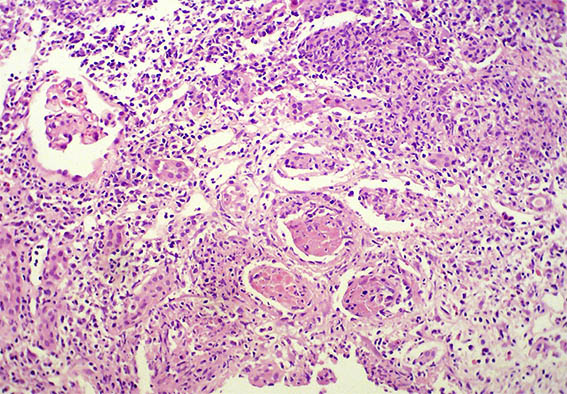

The patient is a 32-year-old man, kidney transplanted 18 months ago due to end-stage renal disease of unknown cause. A cellular rejection episode was evidenced in the first year. Good kidney function in the last control (16 post-transplantation months). Now in a new control the serum creatinine has risen to 1.9 mg/dL. Mild proteinuria and microscopic hematuria, no other abnormalities.

See the images of the renal allograft biopsy.

Figure 1. H&E, X100.